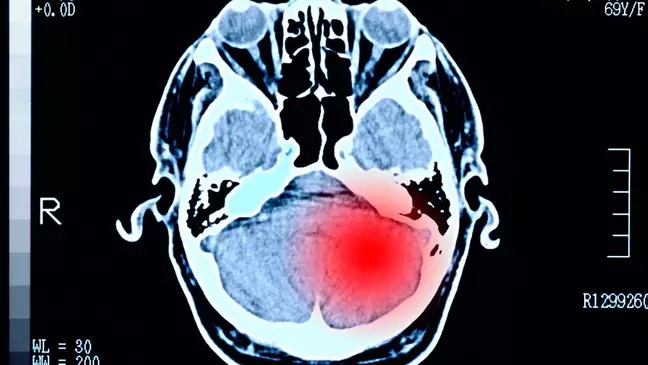

Tumor cerebral;

Segundo o professor Stark, os tumores que representam o maior desafio para adolescentes e adultos jovens são os tumores cerebrais e os carcinomas, principalmente os localizados no aparelho digestivo.

"Os tumores cerebrais são um desafio porque as possibilidades de tratamento e o prognóstico de recuperação são extremamente ruins", diz o especialista.

De acordo com o serviço público de saúde britânico (NHS), os tumores cerebrais podem se manifestar com dores de cabeça, convulsões, tonturas, náuseas recorrentes, problemas de memória, alterações de personalidade, fraqueza progressiva e paralisia em uma parte do corpo e problemas de visão ou fala.